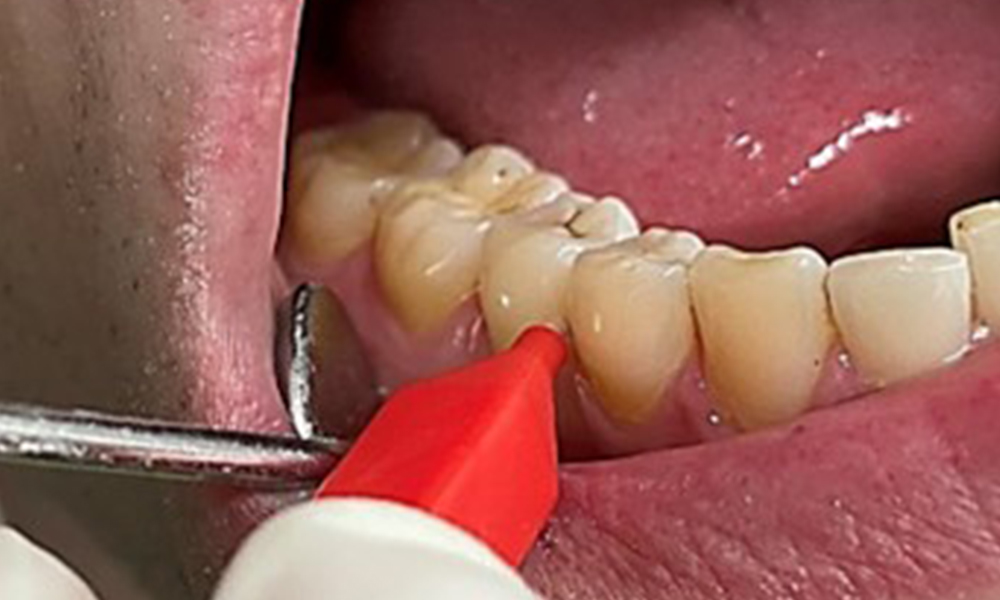

Interdental cleaning with appropriate brushes or dental floss to remove interdental biofilm during the dental appointment is indispensable (Fig. 14).